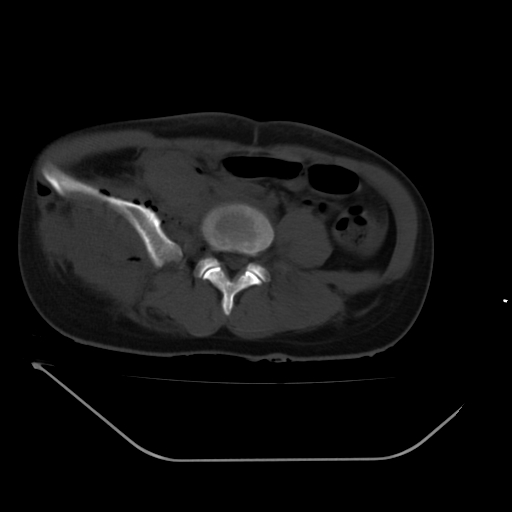

以下是引用liuyue在2008-7-19 13:02:00的发言:[br]1.肝右叶后下段及右肾挫裂伤伴腹腔积血。[br]2.右侧多发性肋骨骨折、横突骨折、右髂骨骨折伴周围软组织挫伤。[br]3.右侧腰大肌肿胀,并可见低密度影,如为气体,则肠道挫裂伤待除外。

以下是引用zhengfaming在2008-7-19 14:42:00的发言:[br]1.肝右叶后下段及右肾挫裂伤伴腹腔积血。脾脏挫裂伤待排[br]2.右侧多发性肋骨骨折、横突骨折、右髂骨骨折伴周围软组织挫伤。[br]3.右侧腰大肌肿胀,并可见低密度影,如为气体,则肠道挫裂伤待除外

以下是引用道哥在2008-7-19 16:52:00的发言:[br]肝右叶后下段及右肾挫裂伤、脾破裂伴腹腔积血。[br]2.双侧多发性肋骨骨折、横突骨折、右髂骨骨折伴周围软组织挫伤。[br]3.右侧腰大肌肿胀,并可见低密度影,如为气体,则肠道挫裂伤待除外。